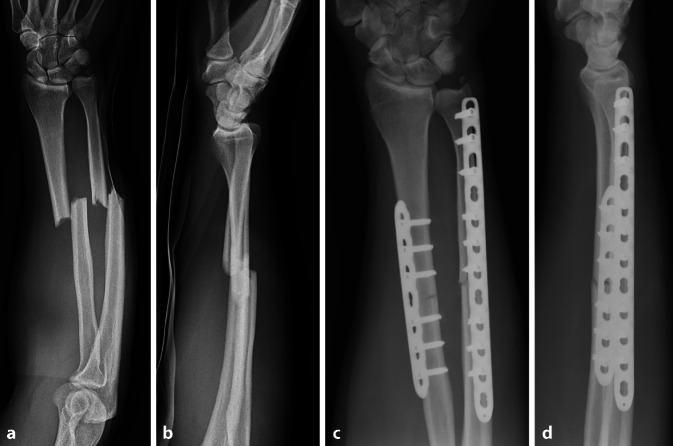

The management of shaft fractures of the upper extremities is an integral part of trauma surgery in the clinical routine. While sport-associated injuries predominate in young adults, the incidence of osteoporotic fractures greatly increases in older patients. Despite established treatment strategies, complications such as wound healing disorders, infections, neurovascular injuries, malalignment, pseudarthrosis and implant failure are frequent. An effective complication management requires detailed knowledge of the morphological features of fractures, individual risk factors and differentiated revision strategies. With the presentation of two clinical cases, we aim to highlight the necessity of individualized treatment concepts. Due to the increasing number of war casualties transferred for secondary treatment to Central Europe, the likelihood of encountering unfamiliar injury patterns, such as blast or gunshot wounds, is rising. This development presents new challenges in daily clinical practice. Physiotherapeutic and occupational therapy support play a central role in achieving favorable functional outcomes following revision surgery for diaphyseal fractures of the upper extremities. In geriatric care, orthogeriatric concepts have significantly decreased mortality and improved mobilization as well as self-sufficiency among older patients. Managing patient expectations and providing close supervision throughout the rehabilitation process are decisive factors for successful recovery.

Abstract Image